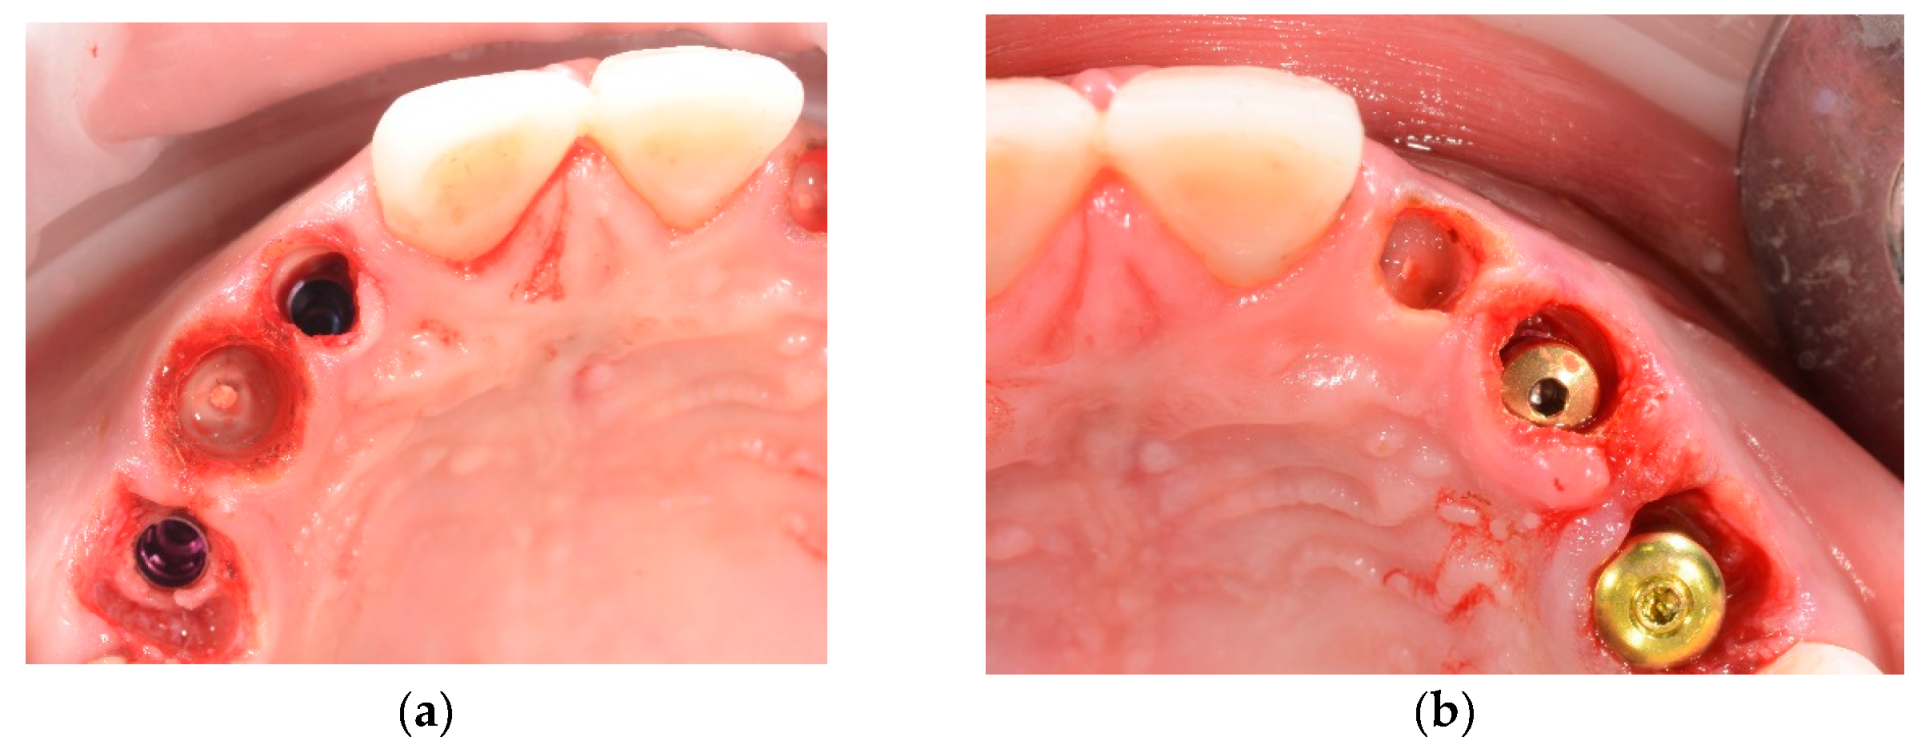

- Upper and lower implant placement with provisional restorations